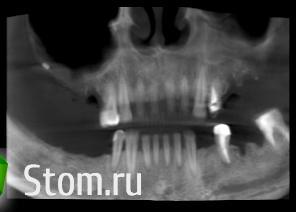

Dr.Politov Опубликовано 24 марта, 2012 Поделиться Опубликовано 24 марта, 2012 Здравствуйте уважаемые коллеги. Очень рад был наткнуться на этот сайт, в частности на форум. Немного о себе: Сам с провинциального города, врач челюстно-лицевой хирург. Пока в начале своего профессионального пути.Выкладываю ОПТГ на первичной консультации (27.12.11г.) и срезы КТ после санации (снятие конструкций, терапевт, пародонтолог) (22.03.12г.). Все удаления выполнялись в середине января. Сейчас этап решения что куда и в какой последовательности. У меня есть план, им я поделюсь ниже, но очень хочется послушать вас, чтобы укрепиться в своём плане или пересмотреть его. Верхняя челюсть:Бюгель, либо двойной синуслифт (после санации левого синуса), через 8 месяцев имплантаты, под несъёмную конструкцию или условно-съёмную.Надеюсь на бюгель согласится ))) Нижняя челюсть:4.5 - 3,75х104.6 - 3,75х104.7 - 4,2х103.4 - 3,75х103.6 - 5.0х10 (но тут вопрос, после удаления прошло 2,5 месяца... ждать или выполнить всё внизу одномоментно и прикрыться Bio-Oss + Bio-Gide? Либо мост на 3.5-3.7 зубы, так как они и так будут покрываться м/к). ps: Он активный курильщик (ещё поэтому я за бюгель на верху) Спасибо, как минимум за внимание ))) Ссылка на комментарий